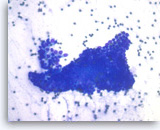

Ductal adenocarcinoma #1,

Pancreas FNA, Direct Smear.

The aspirates show single and clusters of malignant epithelial cells. The clusters are three-dimensional with overlapped nuclei. A few histiocytes are seen in the background.

20X